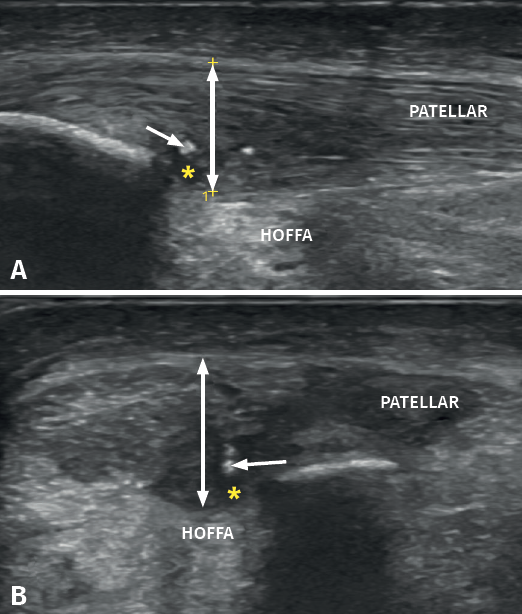

It is also common to identify cortical irregularities in the proximal enthesis of the tendon at the point where it joins the patella, involvement of the paratendon and adherences to Hoffa's fat pad. Any calcifications will be seen as white hyperechogenic zones (Figure 5).

Figure 5. Ultrasound study with high-resolution linear probe in longitudinal (A) and cross-sectional view (B). The double arrow shows increased tendon thickness associated to intra-substance lesions (asterisk) and calcifications (arrow).